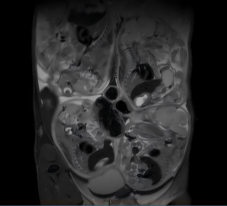

通过T1/T2加权成像,清晰呈现小鼠器官解剖结构,适用于肿瘤、心血管、骨骼等系统的形态学评估。

常规T2序列扫描(怀孕小鼠)

清晰显示胎盘结构、胚胎轮廓及羊水分布